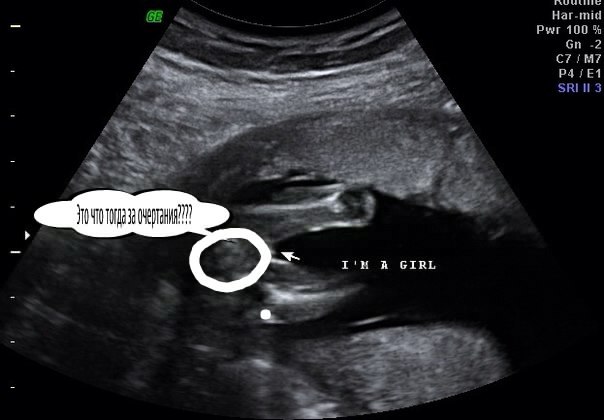

УЗИ, КТГ, доплерКогда нам было 16 недель мы пошли на

узи и нам сказали что у нас 100% девочка

но по фото мне кажется не похоже на

девочку. Вот хочу что бы вы посмотрели

ведь часто бывает что ошибочно.